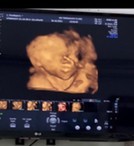

30 weeks ลูกไม่ให้ความร่วมมือเลย เอาแต่ที่เห็น(เท้า)มาบังหน้าเต็มๆเลยยยย 555